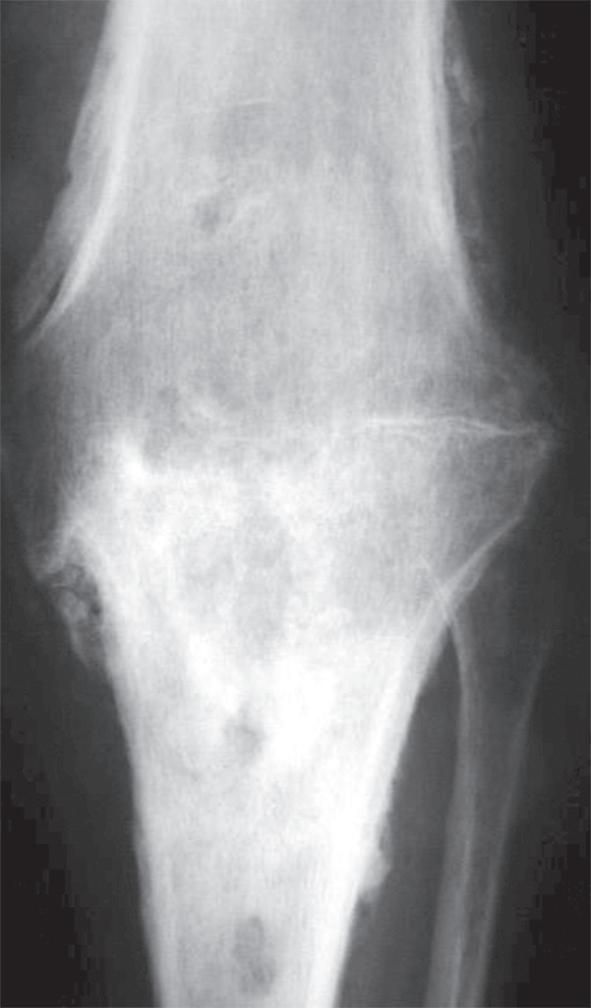

Obr. 19.2: Varózní deformita pravého kolenního kloubu (levé koleno již po korekci osy v rámci implantace náhrady kolenního kloubu) – (a) a rentgenový nález úhlové deformity s nálezem pokročilých artrotických změn (b)

147 kapitola 19 kapitola 19

a)

b)

Obr. 19.3: Valgózní deformita kolenního kloubu (a) a rentgenový  nález úhlové deformity s nálezem pokročilých artrotických  změn (b)

(předozadní a bočná). Na rentgenovém snímku se gonartróza zpočátku projevuje přihrocením interkondylické eminence a subchondrální sklerózou v místě přetížení, později zúžením, případně až zánikem kloubní štěrbiny, vznikem osteofytů, pseudocyst a případnou úhlovou deformitou. Dle nálezu rovněž klasifikujeme stupeň gonartrózy podle Kellgrena-Lawrence (viz kap. 17, obr. 19.4), což má praktický význam v indikaci farmakoterapie i balneoterapie.